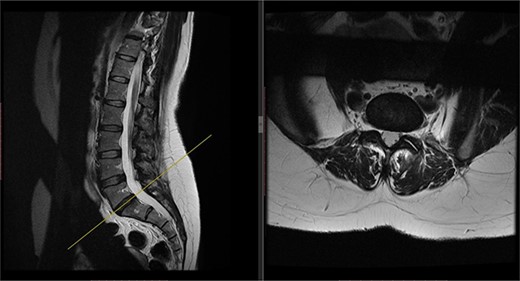

Postoperatively, the patient developed severe radiculopathy down the left leg and required opiates. The patient could not move the left leg and was unable to mobilize. X-rays showed the implants were in position (Fig. 3), but the information from a fresh MRI scan was limited due to metal artefact (Fig. 4). With ongoing, unrelenting pain, she was returned to theatre on the fourth postoperative date, and the wound was re-explored. Intraoperatively, no dural tear was identified, the nerve roots were free, and the screws appeared in position. She was then discharged home after ten nights in hospital, instead of the standard three nights that would be common practice.

Postoperative X-ray of the lumbar spine performed in January 2017, showing the implants in place.

Postoperative MRI of the lumbar spine performed in January 2017. Interference from the metallic pedicular screws limited the scans clarity.